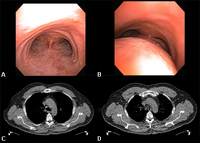

Динамический коллапс дыхательных путей: A. бронхоскопическая проекция на вдохе; B. бронхоскопическая проекция на выдохе, которая показывает динамический коллапс дыхательных путей; C. КТ грудной клетки, которая показывает нормальные дыхательные пути на вдохе; D. КТ грудной клетки, которая показывает значительный коллапс дыхательных путей на выдохе

Из коллекций Хосе Фернандо Сантакруза, дипломированного врача, члена Американской коллегии специалистов в области торакальной медицины, DAABIP, и Эрика Фолка, дипломированного врача, магистра наук; используется с разрешения